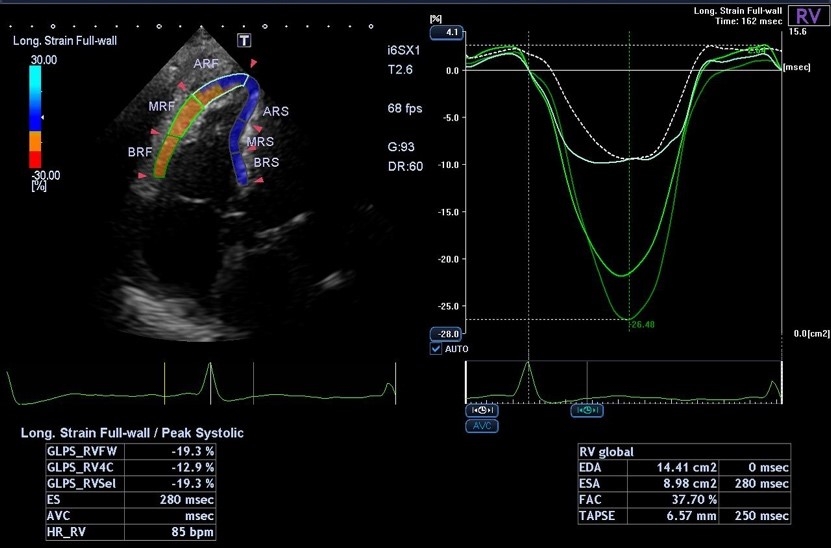

心臓エコーでは、心筋梗塞や狭心症による心臓の壁運動異常や心機能の評価、大動脈弁狭窄症や僧帽弁逆流症等の弁膜症の重症度評価を行います。当院では心臓の収縮機能評価としてストレイン解析を使用しています。心筋は立体的に収縮するため、視覚的に評価が難しいのですが、ストレイン解析により視覚的に評価できない心筋の長さや壁厚の変化を定量的に解析でき、心筋障害を捉えることが可能になります。

また202111月からキャノンの最新機種である超音波検査装置(Aplio i-series Prism Edition)を導入しました。これにより最新技術である右室・左房・右房のストレイン解析が可能となりました。